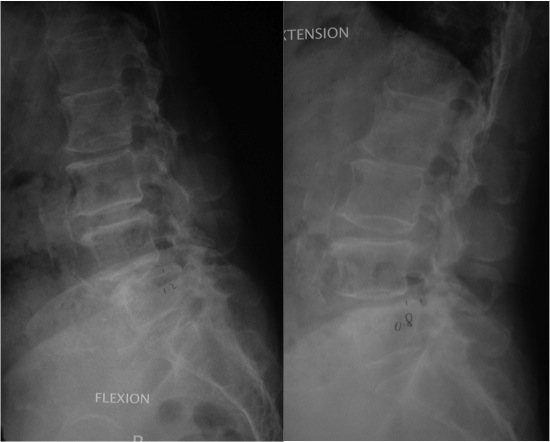

■這是一位七十多歲婆婆的X光片,從中可見在腰第四、五椎管處有退化性滑脫。不可以靠外力復位。